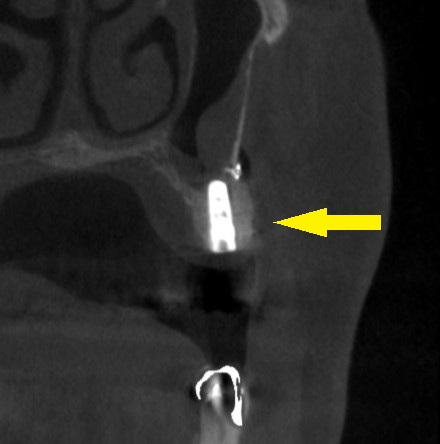

ご了承いただけましたので、本日骨造成術と同時にインプラント埋入術を施行しました。

下の写真右が手術後のCTです。